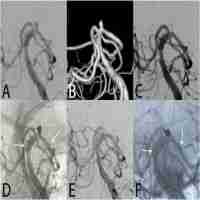

| Abstract | This study was designed to assess the effect of the Enterprise stent on progressive occlusion of wide-necked aneurysms and to evaluate the association between dubious factors and progressive occlusion, which is a consecutive, retrospective, single-center study. Data from 468 patients with 495 wide-necked aneurysms, who had undergone Enterprise stent-assisted coiling (SAC) were reviewed, and the clinical outcomes and the angiographic results were analyzed. A 14-month clinical follow-up was achieved in 421 of the 468 patients (90.0%), showing modified Rankin Scale (mRS) 0–1 in 364 (86.4%), mRS 2 in 17 (4.1%), mRS 3 in 17 (4.1%), mRS 4–5 in 9 (2.1%), and mRS 6 in 14 (3.3%) patients. Overall, the morbidity and mortality were 10.2% and 3.3%, respectively. Initial angiographic results showed Raymond scale (RS)1 in 273 (55.2%), RS2 in 194 (39.2%), and RS3 in 28 (5.6%) patients. Eight-month angiographic follow-up was available in 394 of 495 patients (79.6%), and RS1 was seen in 315 (79.9%), RS2 in 65 (16.5%) and RS3 in 14 (3.6%) cases. At the end of the follow-up, 115 of the 165 (69.7%) patients with initial RS2 and RS3 showed progressive occlusion. Statistical analysis showed no significant difference between progressive occlusion and age (p = 0.654), sex (p = 0.016), aneurysm diameter (p = 0.010), neck size (p = 0.124), dome-to neck ratio (DNR) (p = 0.018) and location (p = 0.001) at the time of follow-up. SAC using Enterprise stent is not only feasible for wide-necked aneurysms, but can achieve a high rate of progressive occlusion with good clinical outcomes at medium-term follow-up. Patient age and aneurysm neck size showed no associated with progressive occlusion at follow-up, while sex, aneurysm diameter, DNR and location were significantly associated with progressive occlusion. |